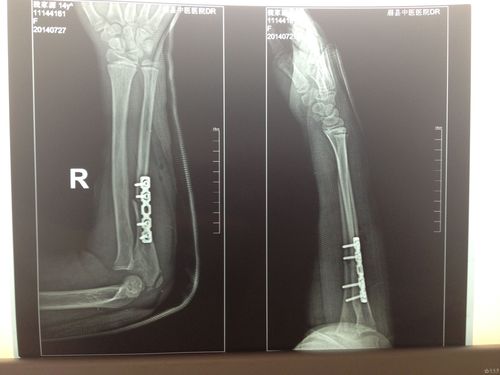

桡骨近端骨折,桡骨小头骨折图片

一例桡骨骨折,可以看到合并近端指骨骨折

注册x 尺骨近端骨折术后第一天复查的片子.术前桡骨头无脱位.